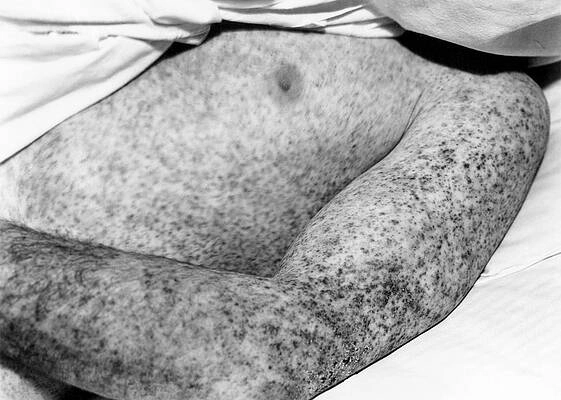

• A faint Colorado Tick Fever rash may appear in some cases, but it is less common than in other tick-borne illnesses like Rocky Mountain spotted fever.

A close-up of a Colorado tick fever rash on skin